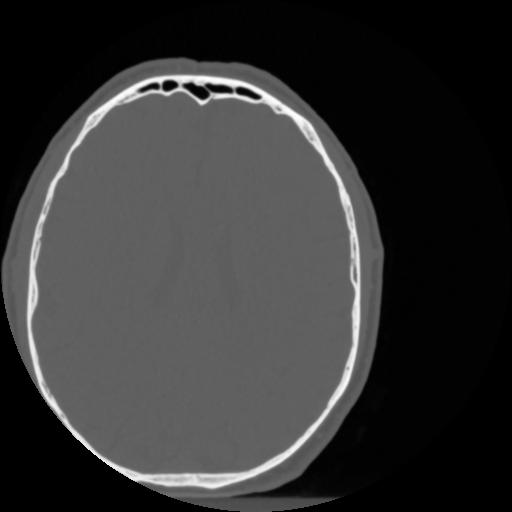

4 CEREBRO,,Vol,0.5,CEREBRO,,